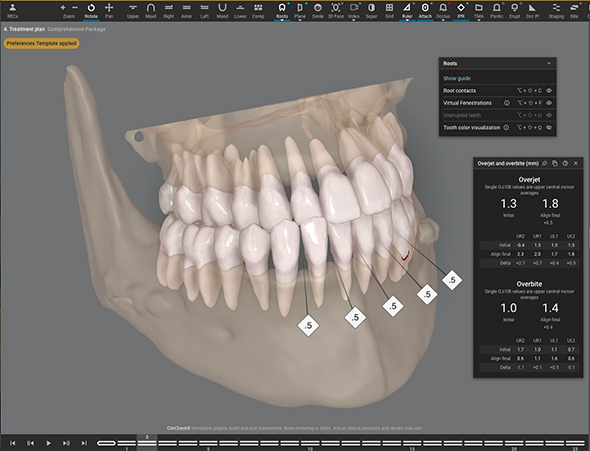

3D Scan and Detailed Explanation

We’ll take a 3D scan of your teeth using our iTero scanner. This allows us to give you a detailed view of your current alignment and provide a visual explanation of the proposed treatment. This advanced technology makes it easier for you to see what to expect from your orthodontic journey.

3D simulation , Video Simulation

We will share your 3D simulation called ClinCheck with you. We now have the technology to simulate your smile not only from your picture but also to create a video simulation, so you can get a detailed, Dynamic Smile Simulation from the treatment made.